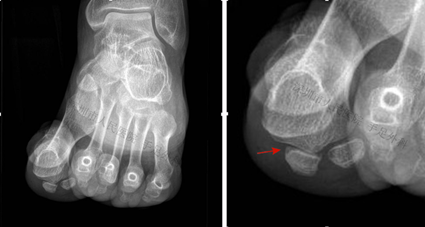

图8:籽骨轴位片示内侧籽骨增生,右图为局部放大图(箭头)

图7:X光片示第二跖骨头无菌性坏死(Freiberg病),跖骨头塌陷,跖骨短缩。上述病变导致拇趾籽骨局部应力增加,导致内侧籽骨增生,最终形成籽骨炎

图6:患者拇外翻畸形,籽骨部位行走时疼痛(箭头),可见痛性胼胝(老茧)